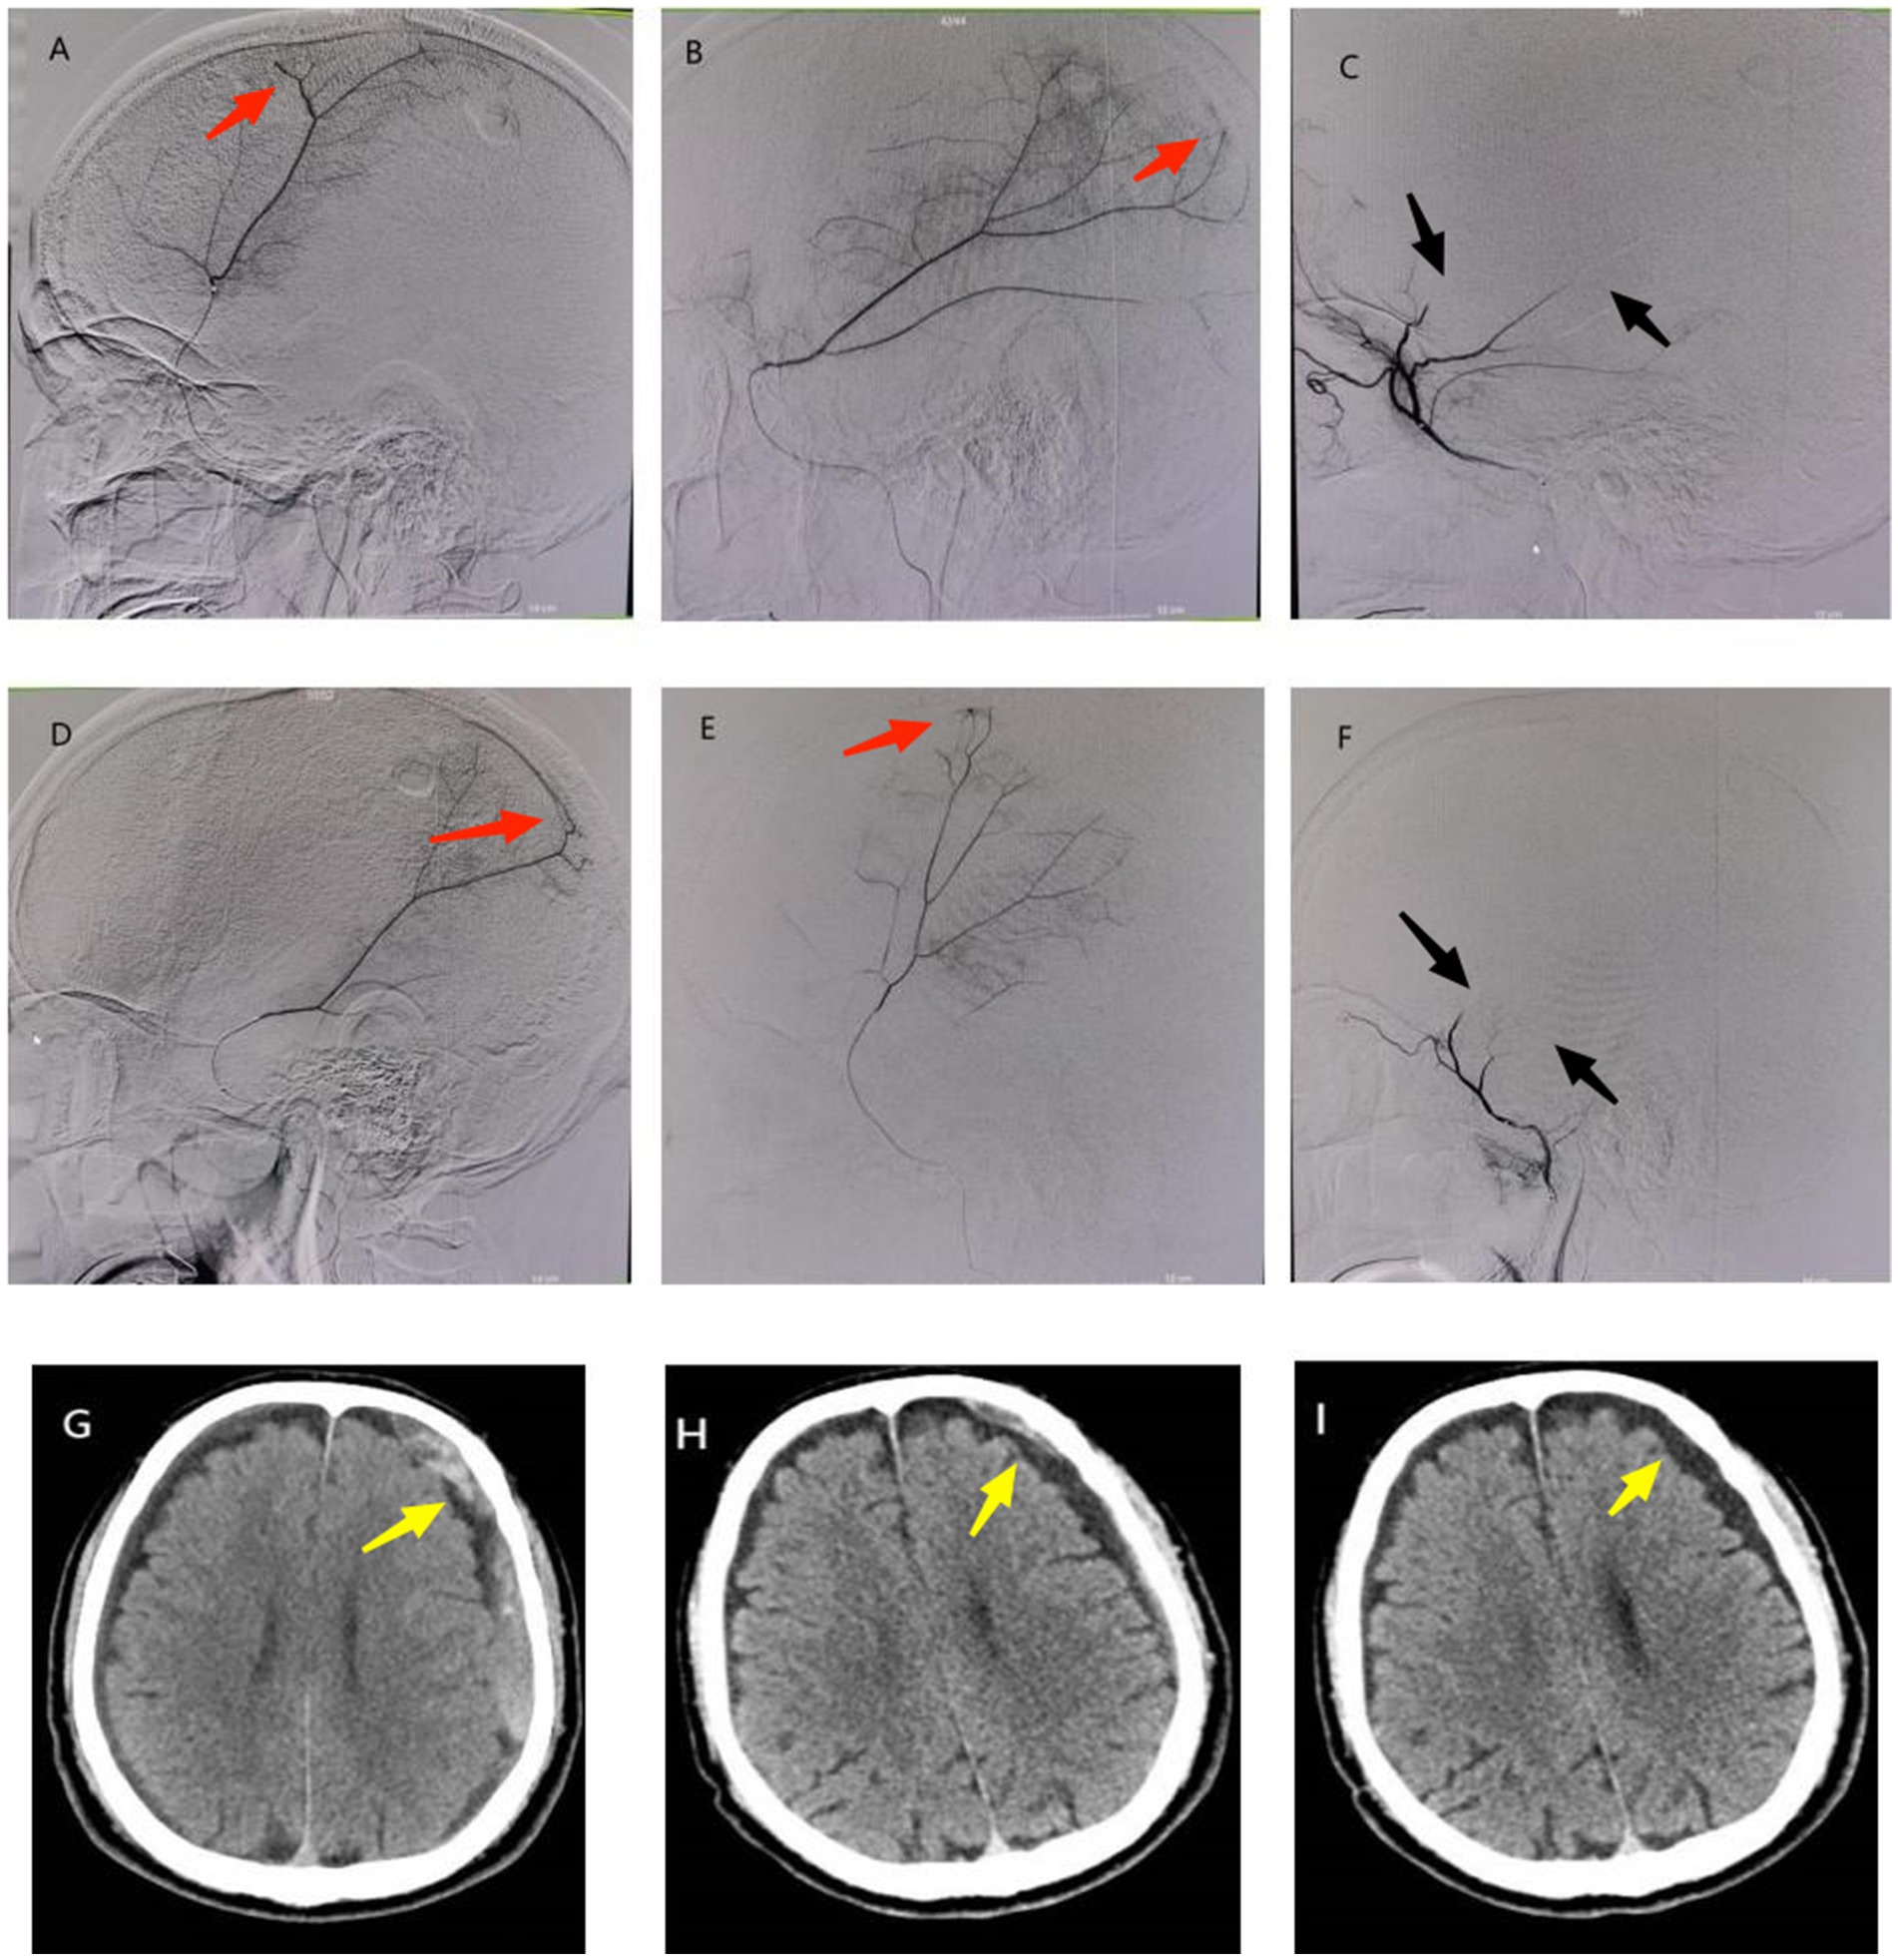

Figure 1. A 70-year-old male patient presented with dizziness and recurrence of left CSDH after burr hole drainage. (A,B) Superselective angiography of the right MMA before interventional procedure showed thickening of distal branches and cotton wool-like staining (red arrow); (D,E) Superselective angiography of the left MMA before interventional procedure showed thickening of distal branches and cotton wool-like staining (red arrow); (C,F) There was no contrast agent filling (black arrow) at the distal end of bilateral MMA branches postoperatively. (G) Preoperative cranial CT showed recurrence of left CSDH (yellow arrow). (H) Cranial CT at 1 month postoperatively showed obvious absorption of subdural hematoma (yellow arrow). (I) Cranial CT at 4 months postoperatively showed subdural hematoma had disappeared with residual subdural effusion (yellow arrow).

Procedure

Under local anesthesia, superselective angiography of the MMA branches demonstrated bilateral distal MMA branch hypertrophy with multifocal cotton wool-like staining (Figures 1A,B,D,E). Subsequent embolization of bilateral distal MMA branches was performed using 100–300 μm Embosphere microspheres (Figures 1C,F). Post-embolization imaging confirmed complete occlusion of the distal MMA branches.

Follow-up

Cranial CT scans at 1 and 4 months post-procedure revealed complete hematoma resolution (Figures 1H,I). The patient achieved full symptomatic recovery with an mRS score of 0.